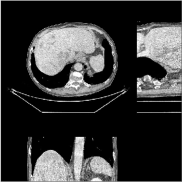

Fig.Β 5 shows the reconstructions and the corresponding error (magnitudes) images (shown for the central axial, sagittal, and coronal planes) for FDK, PWLS-EP, and PWLS-ULTRA () with the patch-based weights. Compared to FDK and PWLS-EP, PWLS-ULTRA significantly improves image quality by reducing noise and preserving structural details (see zoom-ins). Fig.Β 6 shows the RMSE for each axial slice in the PWLS-EP and PWLS-ULTRA (with the weights ) reconstructions. PWLS-ULTRA clearly provides large improvements in RMSE for many slices, with greater improvements near the central slice.

Section IV.E and Table III of [60] compared the performance of various methods for low-dose cone-beam (3D) CT reconstruction, for the XCAT phantom volume. Fig.Β 13 shows the reconstructions and the corresponding error (magnitudes) images (shown for the central axial, sagittal, and coronal planes) at for FDK, PWLS-EP, PWLS-ST (with ), and PWLS-ULTRA () with patch-based weights . PWLS-ULTRA provides better reconstructions and reconstruction errors compared to the conventional FDK and the non-adaptive PWLS-EP. PWLS-ULTRA also outperforms the proposed PWLS-ST scheme, and provides sharper reconstructions of image edges (see zoom-ins).